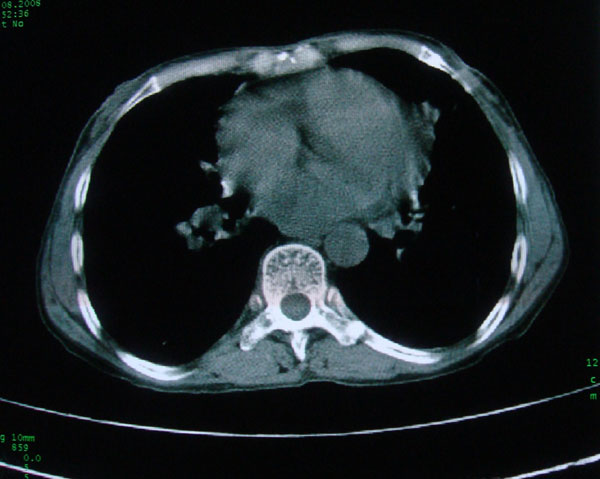

标题: CT15046:F59Y,咳嗽间断咳血丝痰就诊. [打印本页]

标题: CT15046:F59Y,咳嗽间断咳血丝痰就诊.

咳嗽\间断咳血丝痰就诊.

考虑支气管扩张并感染

1慢支伴感染;右下肺周围型肺癌。

本例应该是“慢性疾病并发多种合并症”即:慢支并感染并支气管扩张征!结合病灶分布 形态分析,不除外合并“继发性肺结核”!

慢性支气管炎伴全小型肺气肿、支气管扩张、感染、间质纤维化。

多考虑支气管扩张并感染,双下肺继发性肺结核不除外